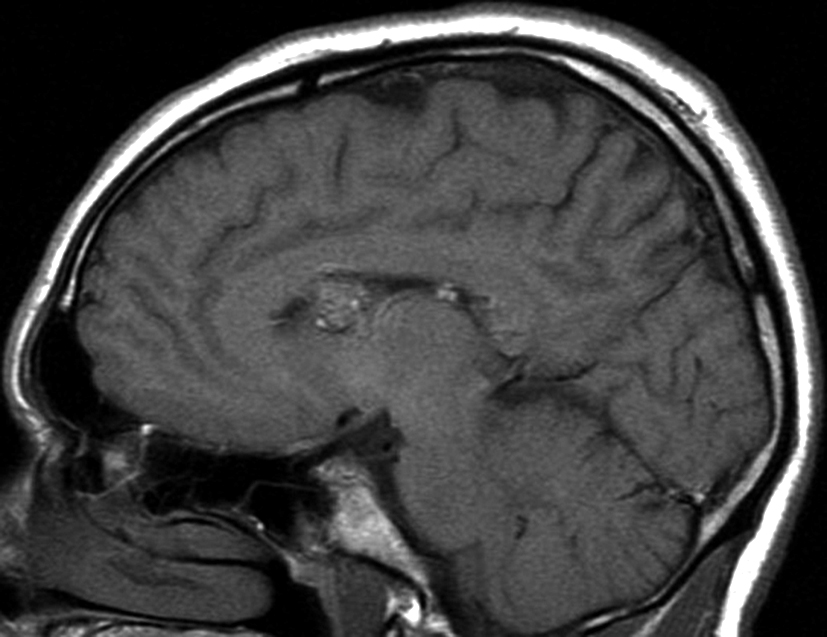

Se presenta el caso clínico de un paciente de sexo masculino, de 36 años de edad, sin antecedentes personales a destacar. Consulta por cefalea holocraneana de larga data, sin déficit neurológico y examen físico normal. Dada la clínica del paciente se realiza una tomografía computada de cráneo sin contraste intravenoso que identifica una lesión bien definida espontáneamente hiperdensa, heterogénea con calcificaciones puntiformes localizada en el asta frontal del ventrículo lateral derecho. No hay edema peri-lesional, efecto de masa ni hidrocefalia (Figura 1- A). Debido a los hallazgos se decide administrar contraste intravenoso, no evidenciándose realce significativo de la lesión (Figura 1- B).

Figura 3

a y b) Imágenes sagitales T1, A. se observa la lesión a nivel del asta frontal de ventrículo lateral derecho y B. se

evidencia la extensión al cuerpo calloso.